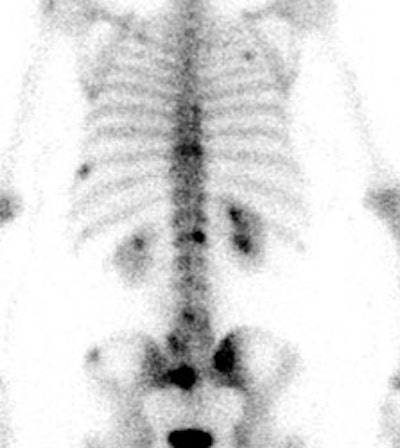

Breast cancer with sclerotic bone mets: The patient below was found to have extensive sclerotic bone metastases on bone scan (left image) and CT (white arrow). Note the lack of tracer uptake on the patient's PET scan (right images). PET is less sensitive for the detection of sclerotic bone metastases, but is superior to bone scan for the detection of lytic lesions. |